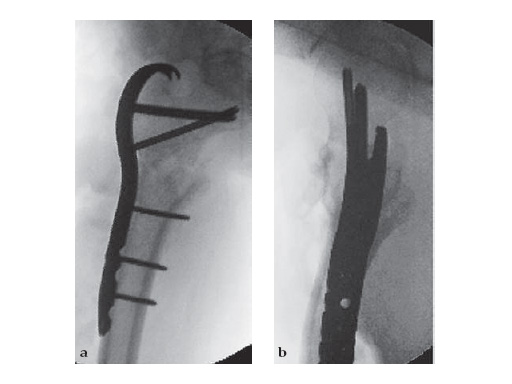

The LCP Proximal Femoral Hook Plate 4.5 is indicated for fractures in the peritrochanteric and subtrochanteric region of the femur that have in common a primary fracture plane that can be tensioned (compressed) utilizing the plate to create a load sharing construct. The most frequent of these patterns are the reverse obliquity and transverse (true intertrochanteric) fractures. The typical insertion technique involves seating of the trochanteric hooks followed by proximal screw insertion (taking into account frontal and sagittal alignment). The side plate is then reduced to the shaft with an atraumatic plate reduction forceps. Horizontal plane alignment (rotation) is then verified and the plate is tensioned utilizing the articulated tension device (ATD). Side plate fixation follows.

46-year-old female with an transverse intertrochanteric fracture

Case provided by Keith Mayo, Tacoma, USAHazards and labeling